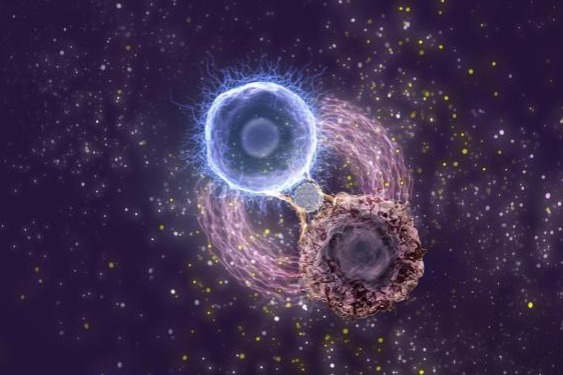

The team developed a novel helper molecule dubbed FACE (Ferritin-based Adhesion and Connection Enhancer), constructed from naturally occurring ferritin protein. This breakthrough emerged from analyzing patient samples that revealed both leukemia cells and immune cells abundantly express the CD71 surface protein. FACE strategically exploits this commonality by binding to CD71 receptors on both cell types, effectively creating a molecular bridge that maintains cellular connection even when cancer cells attempt to hide.

Dr. Wei Wei, lead researcher on the project, explained: “FACE functions as both a microscopic bridge and powerful biological adhesive. When leukemia cells reduce their identifiable markers to escape detection, FACE ensures CAR T-cells maintain their grip and complete their therapeutic mission.”